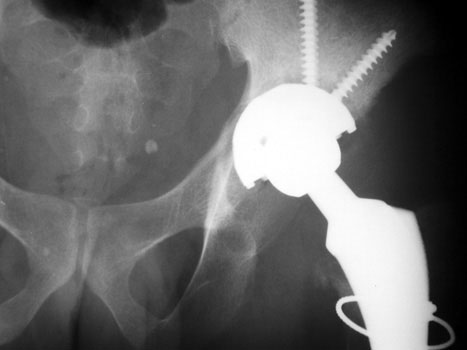

Resection of hardware, cement spacer placement

Cement spacers are antibiotic impregnated, allowing for local dispersal of antibiotics.

• Maintain leg length

• Minimize dead space

• Preserve soft tissue planes

• Facilitate ease of revision arthroplasty

Cement spacers are fabricated in the surgical suite using methylmethacralate cement impregnated with antibiotics sensitive to cultured organisms. A Rush rod is cut and bent to 120 degrees to mimic the femoral neck-shaft angle. Antibiotic impregnated cement is placed into a blue bulb syringe which simulates the femoral head contour and allowed to dry. The plastic is then removed. A second batch of cement is prepared and formed around the femoral shaft portion of the Rush rod.